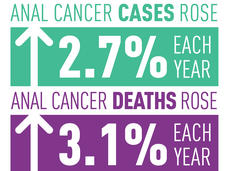

Anal Cancer Incidence and Deaths Are Rising in the United States

The number of cases and deaths from anal cancer have been on the rise in the United States since 2001, according to a new study. The increases have been especially rapid in two segments of the population.